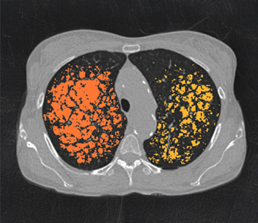

Built on advanced capabilities in lung segmentation and quantification, our AI technology interprets thoracic CT data with anatomical precision - capturing airway trees, parenchymal patterns, and vascular structures, even in severely diseased lungs.

- Quantitative analysis of complex lung patterns and diseased regions